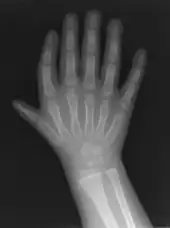

| Finger-like appearance | |

Triphalangeal thumb (TPT) is a congenital malformation where the thumb has three phalanges instead of two. The extra phalangeal bone can vary in size from that of a small pebble to a size comparable to the phalanges in non-thumb digits. The true incidence of the condition is unknown, but is estimated at 1:25,000 live births.[1] In about two-thirds of the patients with triphalangeal thumbs, there is a hereditary component.[2] Besides the three phalanges, there can also be other malformations. It was first described by Columbi in 1559.[3]

The triphalangeal thumb has a different appearance than normal thumbs. The appearance can differ widely; the thumb can be a longer thumb, it can be deviated in the radio-ulnar plane (clinodactyly), or thumb strength can be diminished. In the case of a five-fingered hand it has a finger-like appearance, with the position in the plane of the four fingers, thenar muscle deficiency, and additional length. There is often a combination with radial polydactyly.